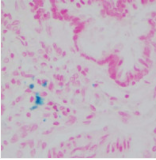

實驗結果:

脂滴呈橘紅色至鮮紅色:細胞核呈深藍色。